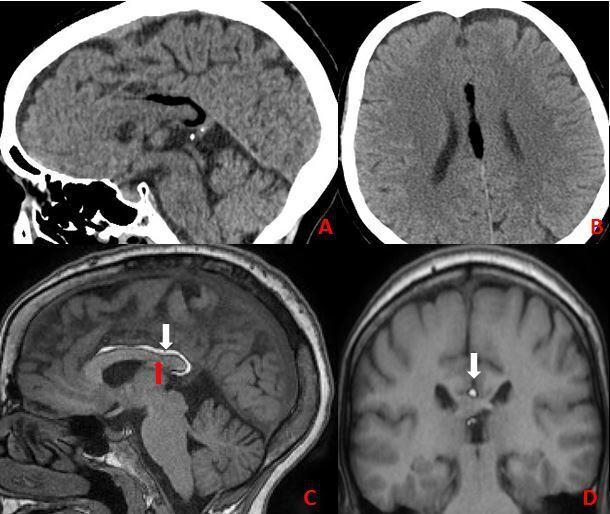

P lipomas are the most habitual location for an intracranial lipoma. They are fat-containing lesions arising from the interhemispheric fissure intimately related to the corpus callosum, which is often abnormal. They originate from aberrant differentiation of the persistent primitive meninx. Most Pericallosal lipomas are asymptomatic and come into clinical attention during neuroradiological investigations for other conditions. MRI is the modality of choice to characterize not only the extent of the lipoma but also the frequently associated agenesis/dysgenesis of the corpus callosum. Pericallosal lipomas can be divided into two groups: The Tubulonodular type and The curvilinear type. Curvilinear lipomas are less common than Tubulonodular. We report the clinical and radiological findings of curvilinear Pericallosal lipoma in two patients with corpus callosum abnormalities revealed incidentally during evaluation following trauma.

胼胝体脂肪瘤是颅内脂肪瘤最常见的部位。它们是起源于大脑半球间裂、与胼胝体密切相关的含脂肪病变,胼胝体常存在异常。它们起源于残留原始脑膜的异常分化。大多数胼胝体脂肪瘤无症状,在因其他疾病进行神经影像学检查时才引起临床关注。MRI不仅是确定脂肪瘤范围的首选检查方法,也是发现胼胝体常伴发的发育不全/发育异常的首选方法。胼胝体脂肪瘤可分为两组:管状结节型和曲线型。曲线型脂肪瘤比管状结节型少见。我们报告了两例在创伤后评估中偶然发现胼胝体异常的曲线型胼胝体脂肪瘤患者的临床和影像学表现。